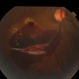

- 28 year old female with sub-ILM hemorrhage and questionable cotton wool spot. Pt states sudden vision loss after being hit in the eye with laser lights at a nightclub. Laser lights also damaged the camera in her iPhone. Will give hemorrhage more time to clear on its own, will discuss treatment options if no improvement at next visit.